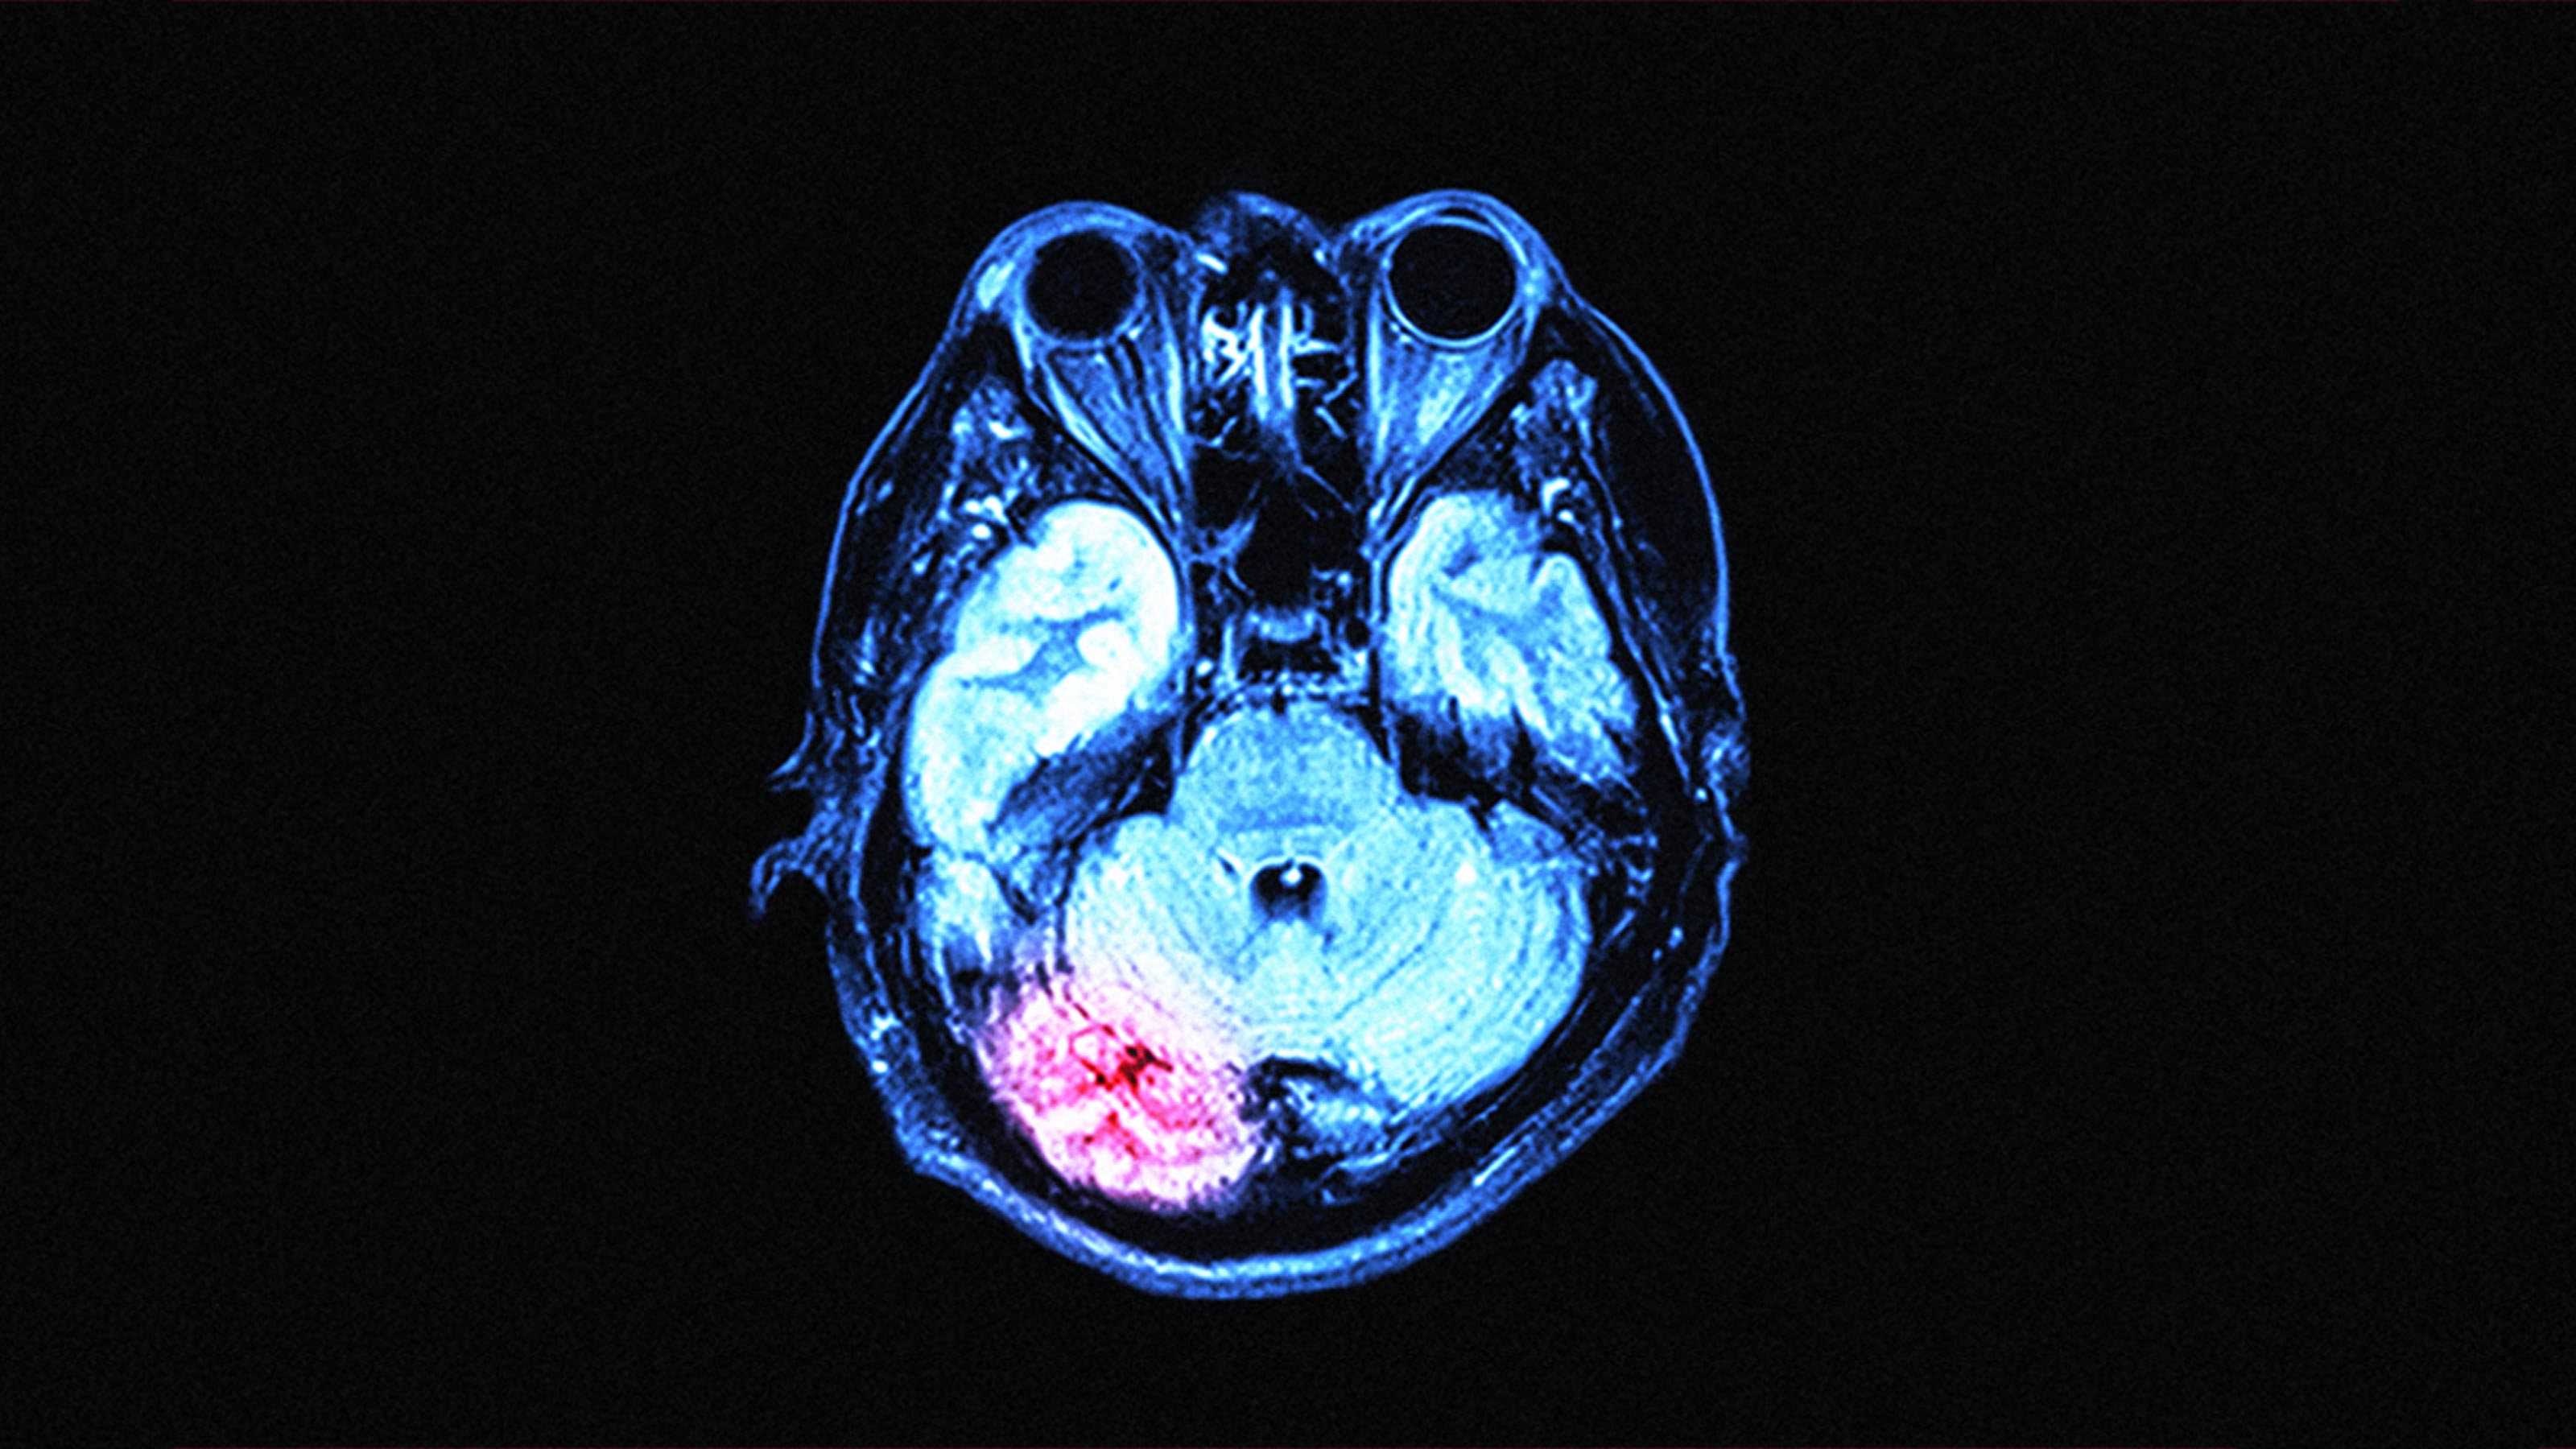

Coronavirus Affects the Brain